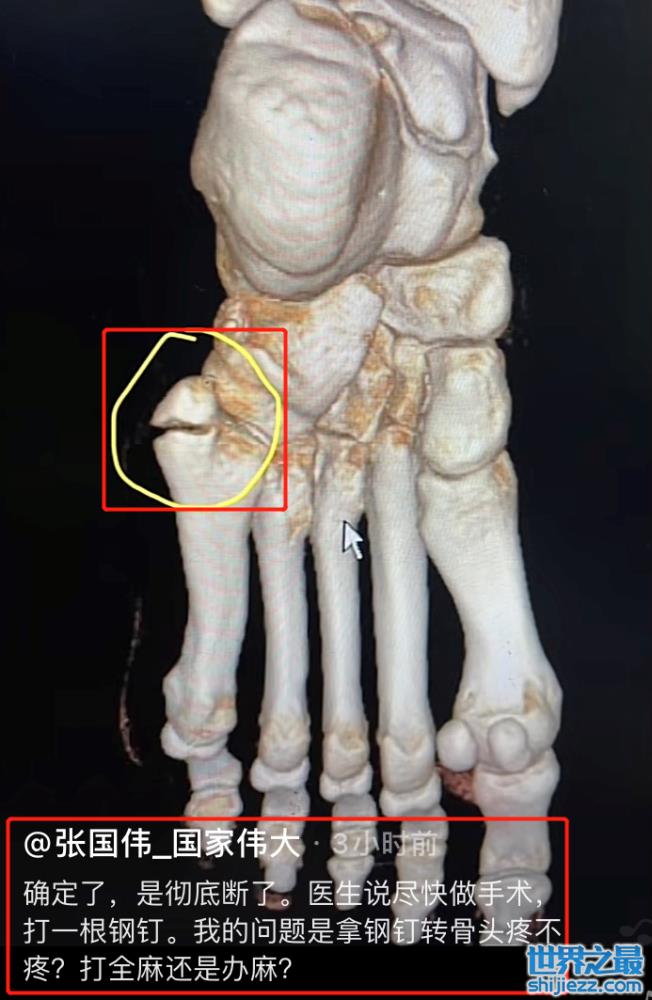

近日,30岁的张国伟在社交平台晒出,医院诊疗的左脚CT照片,并且配文道;“确定了,彻底断了,医生说要尽快做手术”,引发热议。

张国伟晒出左脚的骨头照片,并用圈将裂缝处圈出来,非常清晰的可以看见最左边的骨头断了。张国伟解释说骨折的原因就是训练太猛了,疲劳导致。可以清晰的看见他的脚上的皮肤还有一些呈暗紫色。

虽然张国伟经历着身体上的伤痛,但他开玩笑般说“打全麻还是打半麻“,感觉不到他有一丝的丧气。他还晒出站在CT检查室的自拍,张国伟穿一件黑色短袖,日复一日的严苛训练,使他的身材更消瘦了,但他仍对着镜头比耶。